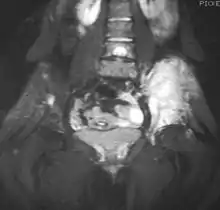

Medical imaging

On conventional radiographs, the most common osseous presentation is a permeative lytic lesion with periosteal reaction.[1] The classic description of lamellated or "onion-skin" type periosteal reaction is often associated with this lesion.[1] In addition, Magnetic resonance imaging (MRI), Computed axial tomography (CT) and PET scan can help fully define the Ewing sarcoma and assess any spread.[1]

MRI will show the full bony and soft tissue extent and relate the tumor to other nearby anatomic structures (e.g. vessels). Gadolinium contrast is not necessary as it does not give additional information over noncontrast studies, though some current researchers argue that dynamic, contrast-enhanced MRI may help determine the amount of necrosis within the tumor, thus help in determining response to treatment prior to surgery. Computed axial tomography (CT) can also be used to define the extraosseous extent of the tumor, especially in the skull, spine, ribs, and pelvis. Both CT and MRI can be used to follow response to radiation and/or chemotherapy. Bone scintigraphy can also be used to follow tumor response to therapy. In the group of malignant small round cell tumors that includes Ewing sarcoma, bone lymphoma, and small cell osteosarcoma, the cortex may appear almost normal radiographically, while permeative growth occurs throughout the Haversian channels. These tumors may be accompanied by a large soft-tissue mass while almost no bone destruction is visible. The radiographs frequently do not shown any signs of cortical destruction. Radiographically, Ewing's sarcoma presents as "moth-eaten" destructive radiolucencies of the medulla and erosion of the cortex with expansion.